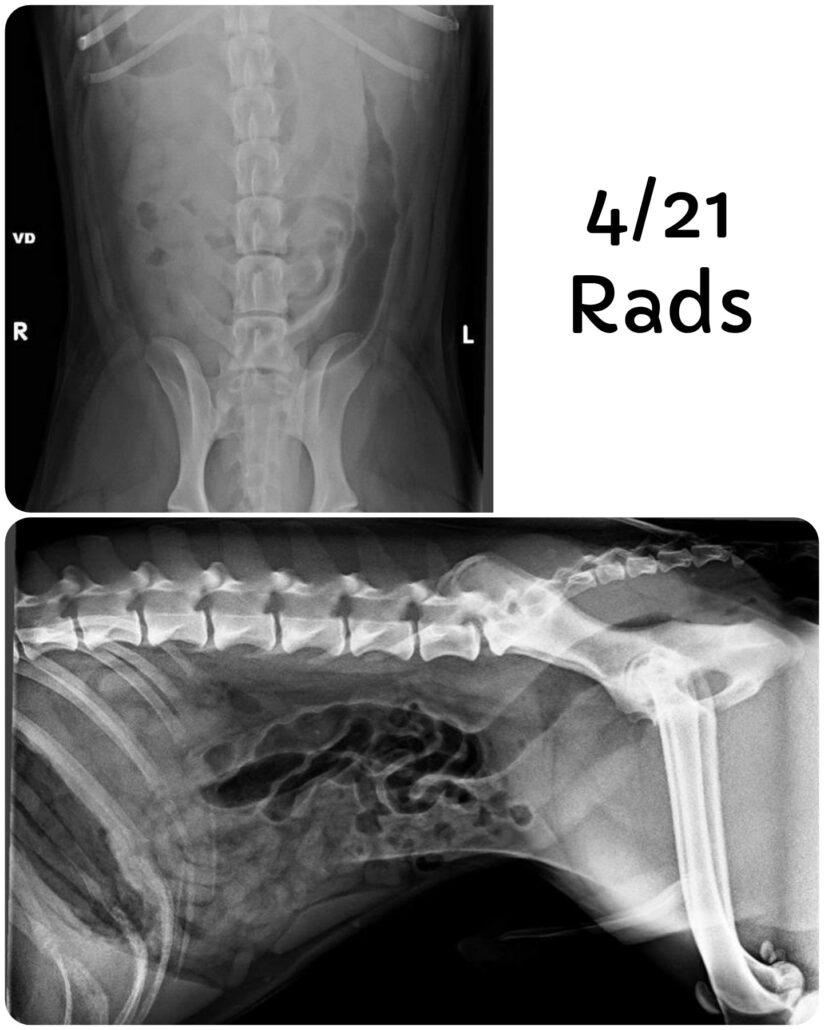

Roadhouse is a very friendly dog and seems to like other dogs and humans. When he first arrived, he was vomiting, bloody diarrhea and not eating. It was noted he had been passing pieces of toys in his stools.

The shelter did an exploratory surgery on April 22 and found nothing in his bowels or stomach. Unfortunately, Roadhouse has continued to vomit, have diarrhea (no longer bloody, but now mucousy) and is still not eating. The veterinarians at the KHS recommend further diagnostics. He is currently being administered Cerenia SID x3 and Metronidazole BID. No background information or information on Roadhouse is unknown.